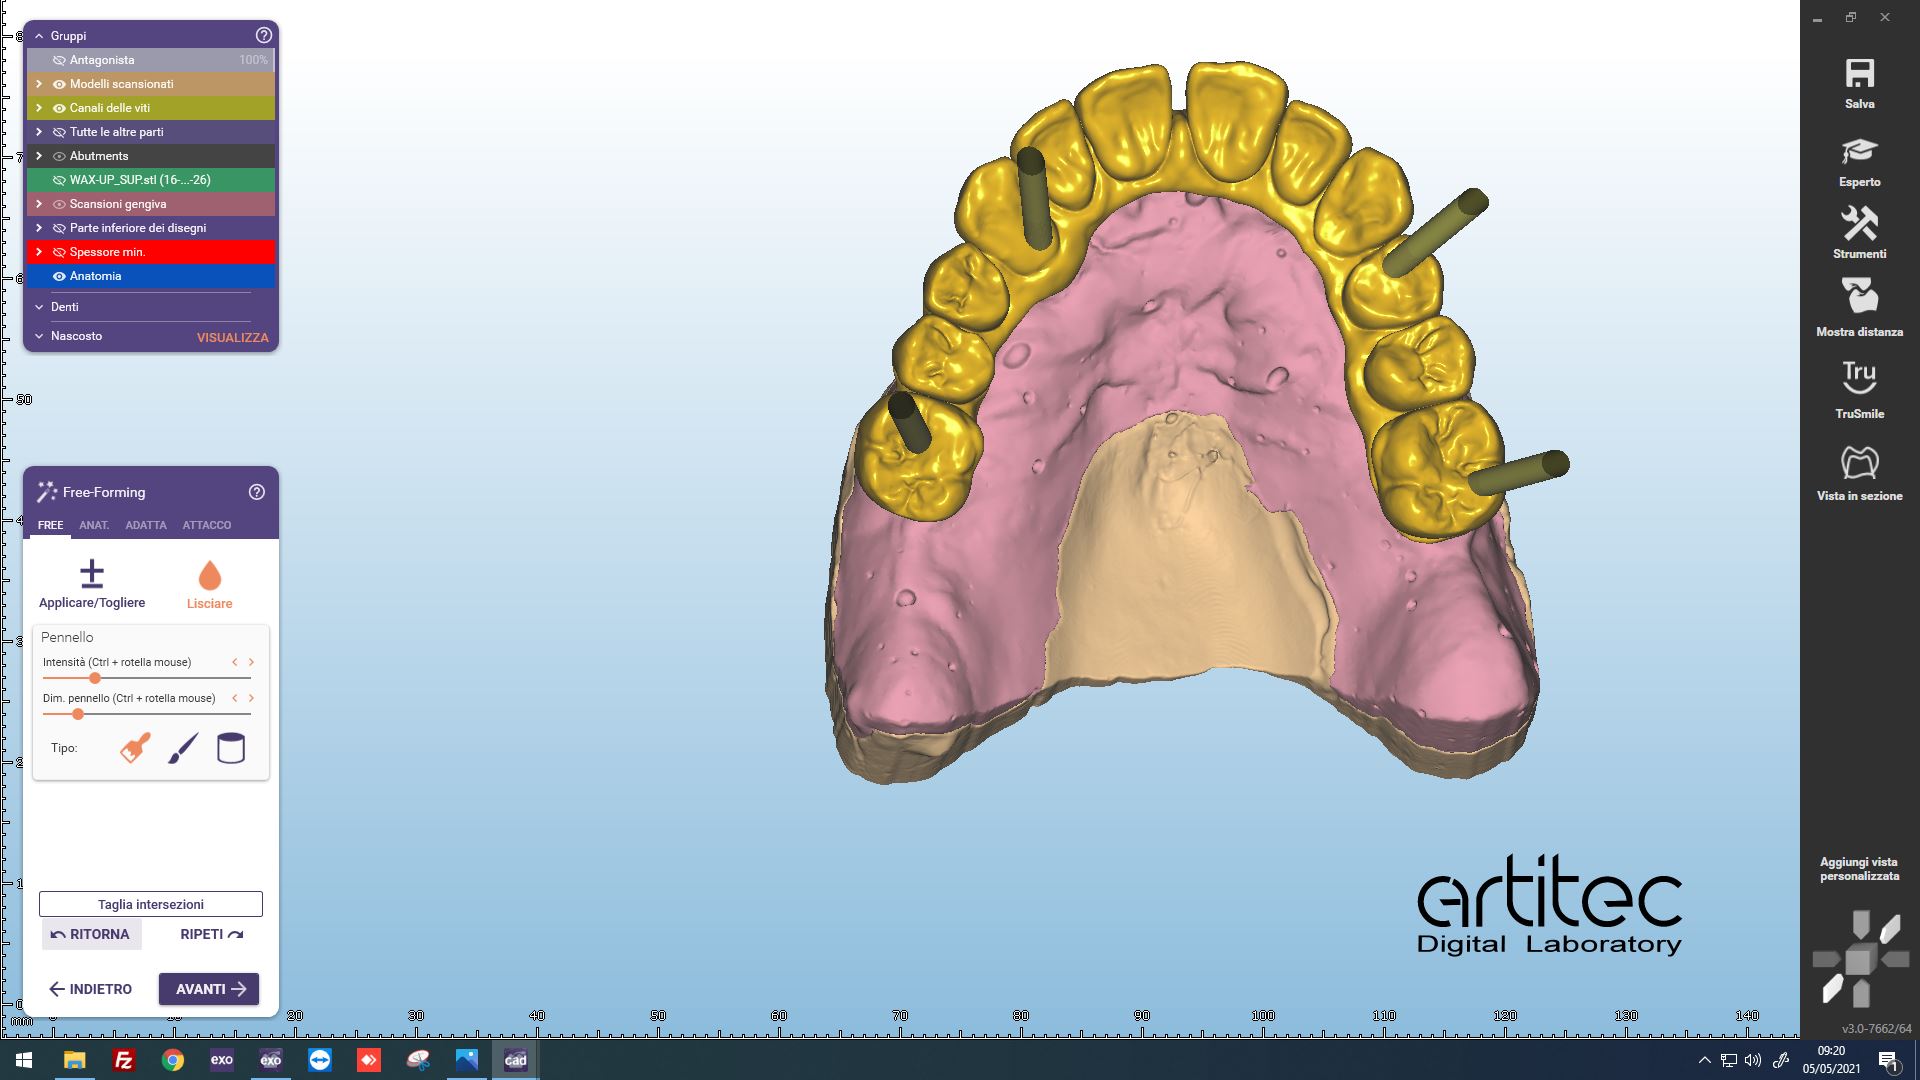

Fig. 6 Posizionamento anatomie CAD/CAM

Fig. 7 Posizionamento dei linker

Fig. 8 Vista occlusale dei linker